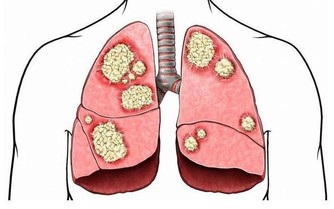

5、抗腫瘤的藥物

環磷酰胺是非常常見的抗腫瘤藥物,它也能夠升高尿酸,容易產生高尿酸血症。